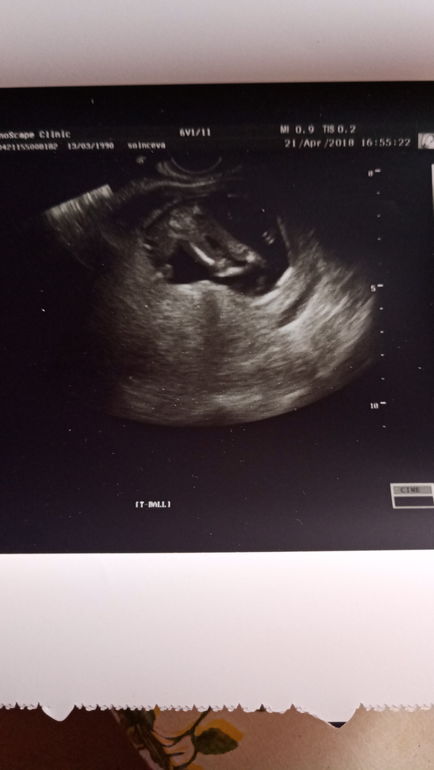

УЗИ, КТГ, доплерДевочки, всем привет, не выдержала пошла на УЗИ, сидели мы на попе, поэтому УЗИ сделали вагинально, сказали 70-80% девочка, ничего не видет от мальчика, сделала фото ножек, а там я и увидела бугорок, не понимаю что это. Может кто из вас понимает. А пока я закрашиваю кружочек розовым, в 20 недель скрининг там или подтвердят или опровергнут, а пока я счастлива безумно, все как и хотела, мама дочки)))

я думаю девочка,а бугорок это скорее клитор он до 17-20 недель торчит заметно(не у всех ,но все же)

Это девчушечка скорее всего) Может плохо видно на фото, Вы на оригинале посмотрите, если между ножек прям кофейное зернышко, то 100% она.